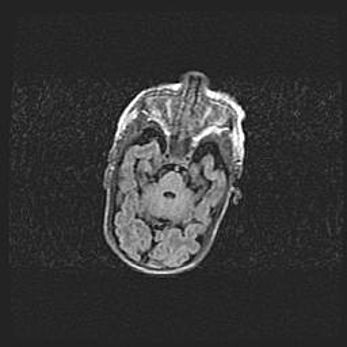

Наружная гидроцефалия с возможной атрофией височных областей.

Возраст: 28 дней

Вес: 3670 г

Пол: мужской

Окружность головы: 38 см

Срок гестации: 40 недель

Гидроцефалия головного мозга у новорожденных – это заболевание, которое характеризуется скоплением избыточного количества спинномозговой жидкости в желудочковой системе головного мозга в результате затруднения её перемещения от места выработки к месту поглощения в кровеносную систему или вследствие нарушения абсорбции. При открытой наружной форме гидроцефалии у новорожденных расширяются и переполняются субарахноидные пространства.

При нормотензивных  формах,  которые,  как  правило,  являются  следствием  перенесенных ишемических  повреждений  паренхимы  мозга,  возможно  сочетание микроцефалии  с нормотензивной гидроцефалией. В основе данных изменений лежит атрофия больших полушарий с преимущественной  локализацией  в  лобно-височных  областях.